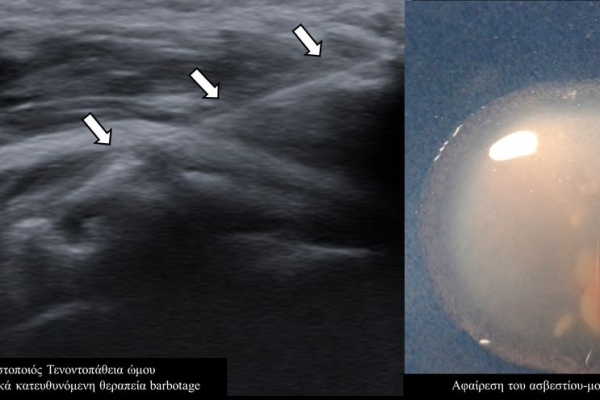

Η υπερηχογραφικά καθοδηγούμενη αφαίρεση των επασβεστώσεων (barbotage) είναι μια ελάχιστα παρεμβατική (minimally invasive) τεχνική θεραπείας για την ασβεστοποιό τενοντοπάθεια. Με τους υπερήχους είναι δυνατός ο εντοπισμός των ασβεστώσεων και η διαδερμική τοποθέτηση μιας βελόνας στο κέντρο της συμπτωματικής ασβέστωσης. Στη συνέχεια γίνεται διαδερμικός τρυπανισμός και επαναλαμβανόμενες πλύσεις του ασβεστίου, με αποτέλεσμα τόσο την αφαίρεση της παθολογικής επασβέστωσης όσο και την αυξηση τοπικά της αιμάτωσης με αποτελεσμα την σταδιακή απομάκρυνση των παραγόντων φλεγμονής-ερεθισμού.